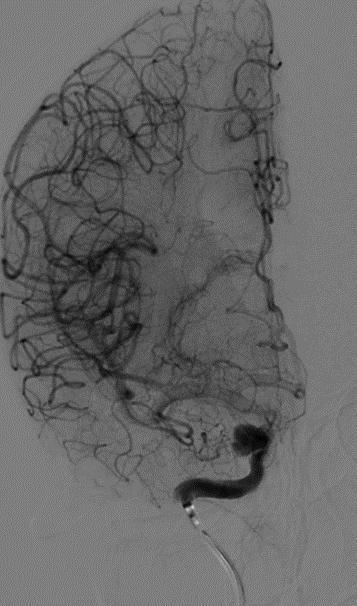

麻醉成功后,患者仰卧,常规消毒,铺巾, Seldinger法穿刺右侧股动脉,置入5F动脉鞘,置入5F造影管行右侧颈内动脉正侧位及3D造影后,更换6F长动脉鞘,6F中间导管在导丝引导下进入右侧颈动脉分叉端并固定。根据3D造影选择工作体位并放大做路图后,T-track微导管在微导丝引导下进入右侧大脑中动脉,经微导管送入4.0×45mm Tubridge®支架,观察 Marker位置后,于颈动脉分叉附近缓慢释放支架。

全脑DSA正侧位造影示血流通畅。

动脉瘤内造影剂滞留,未填弹簧圈。行Xper CT,观察见支架完全打开,贴壁良好。术程顺利结束。